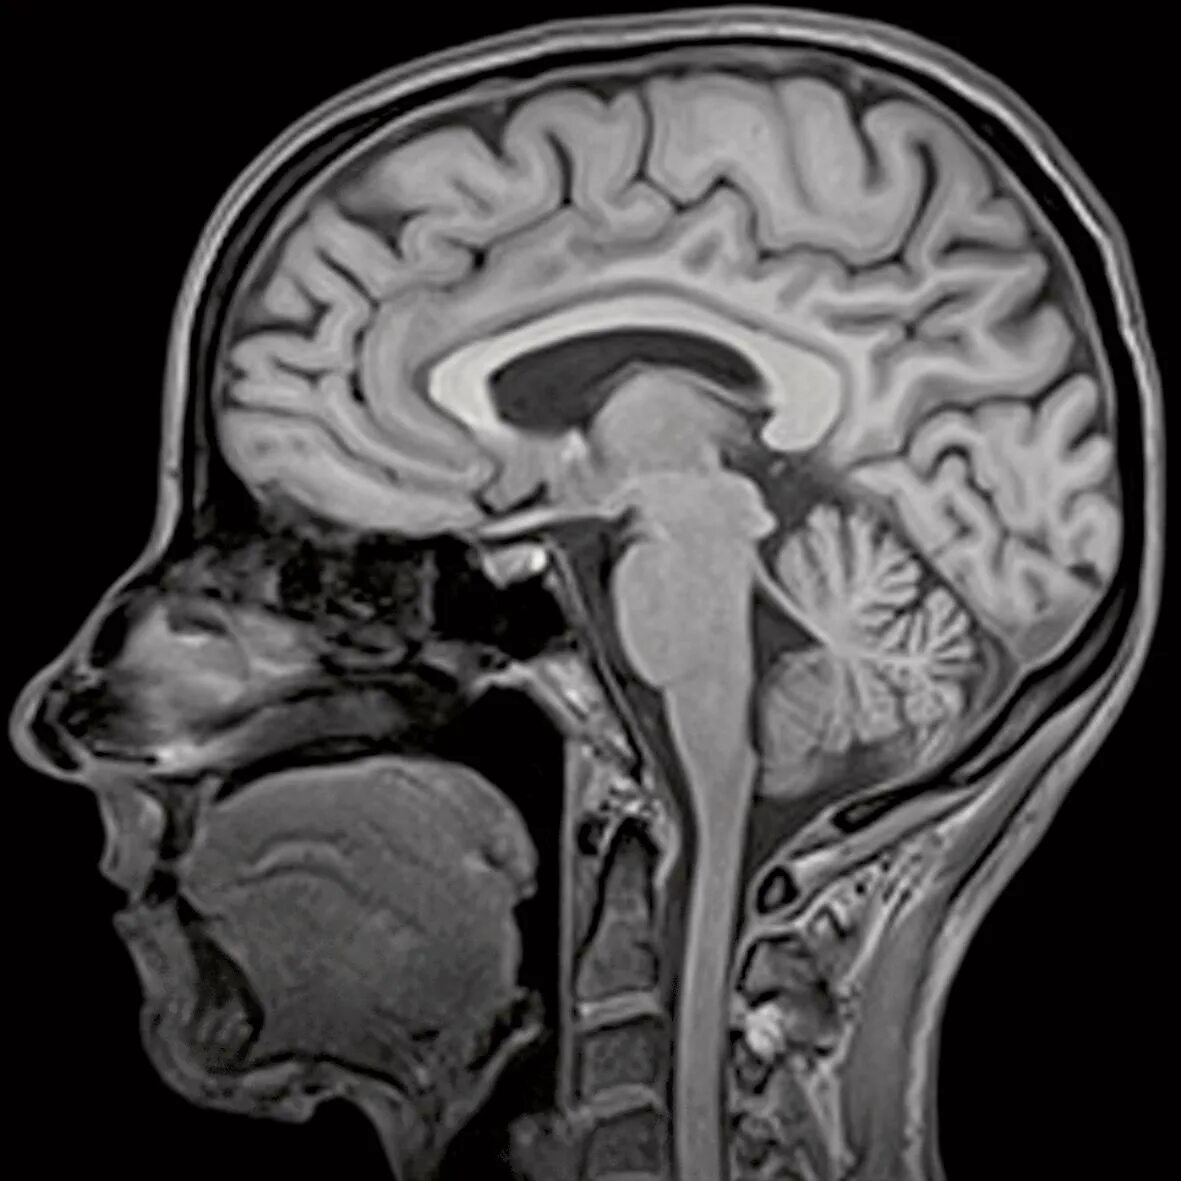

Мрт головы спб